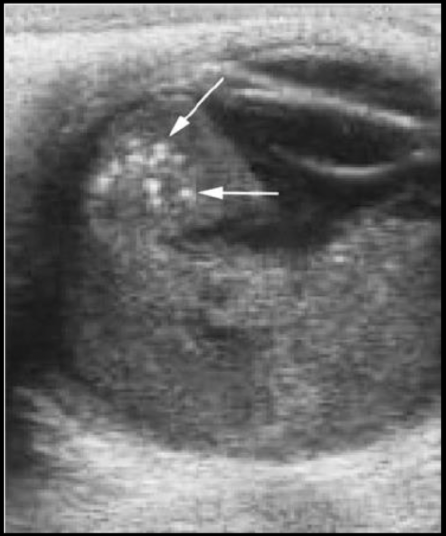

El USG es útil para dx de retinoblastoma?

Sí, podemos ver lesiones hiperecogénica con calcificaciones

Que estudio es y que se puede ver

USG que muestra retina doblada y brillante

De qué enfermedad sospechas?

Desprendimiento de retina